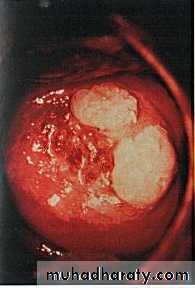

Genital warts

Florid vulval warts

Cervical warts